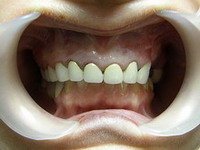

Estetica rezolvata cu coroane din

ceramica pe zirconiu